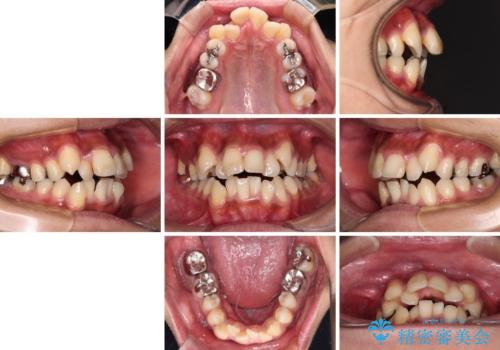

八重歯と開咬 ワイヤー装置での抜歯矯正

- 前歯のデコボコと八重歯、開咬を気にして来院された患者様です。

骨格的に下顎骨が上顎骨に対して後退位であったため、上顎の左右第一小臼歯を抜歯し、デコボコを改善するとともに開咬を改善していくこととしました。